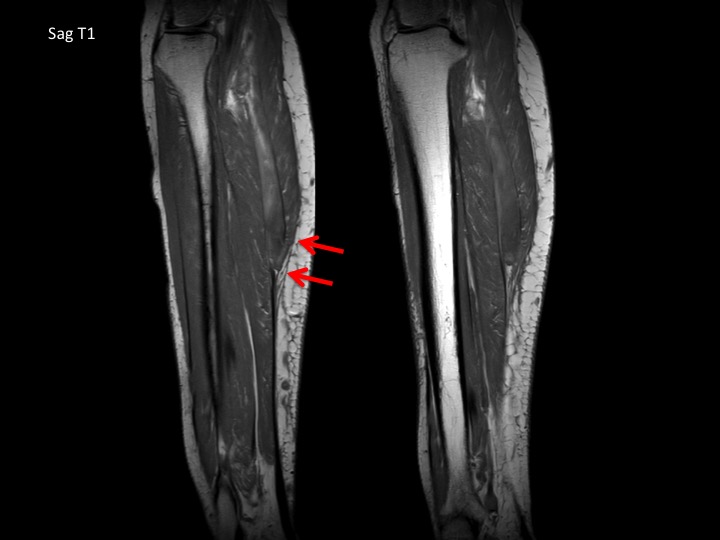

60F 3 weeks calf pain, suspect DVT

No DVT. Very subtle subacute full thickness tear at the distal myotendinous junction of the medial head gastrocnemius with 1.5 cm retraction at the tear and mild muscle edema. There is a subacute hematoma in the intermuscular fat planes (outlined in yellow) which is almost isointense to muscle, with a dark rim on ax T2FS and peripheral bright rim on T1. Easy to miss. Reference article.

medial head of gastrocnemius muscle ( RID2921 )